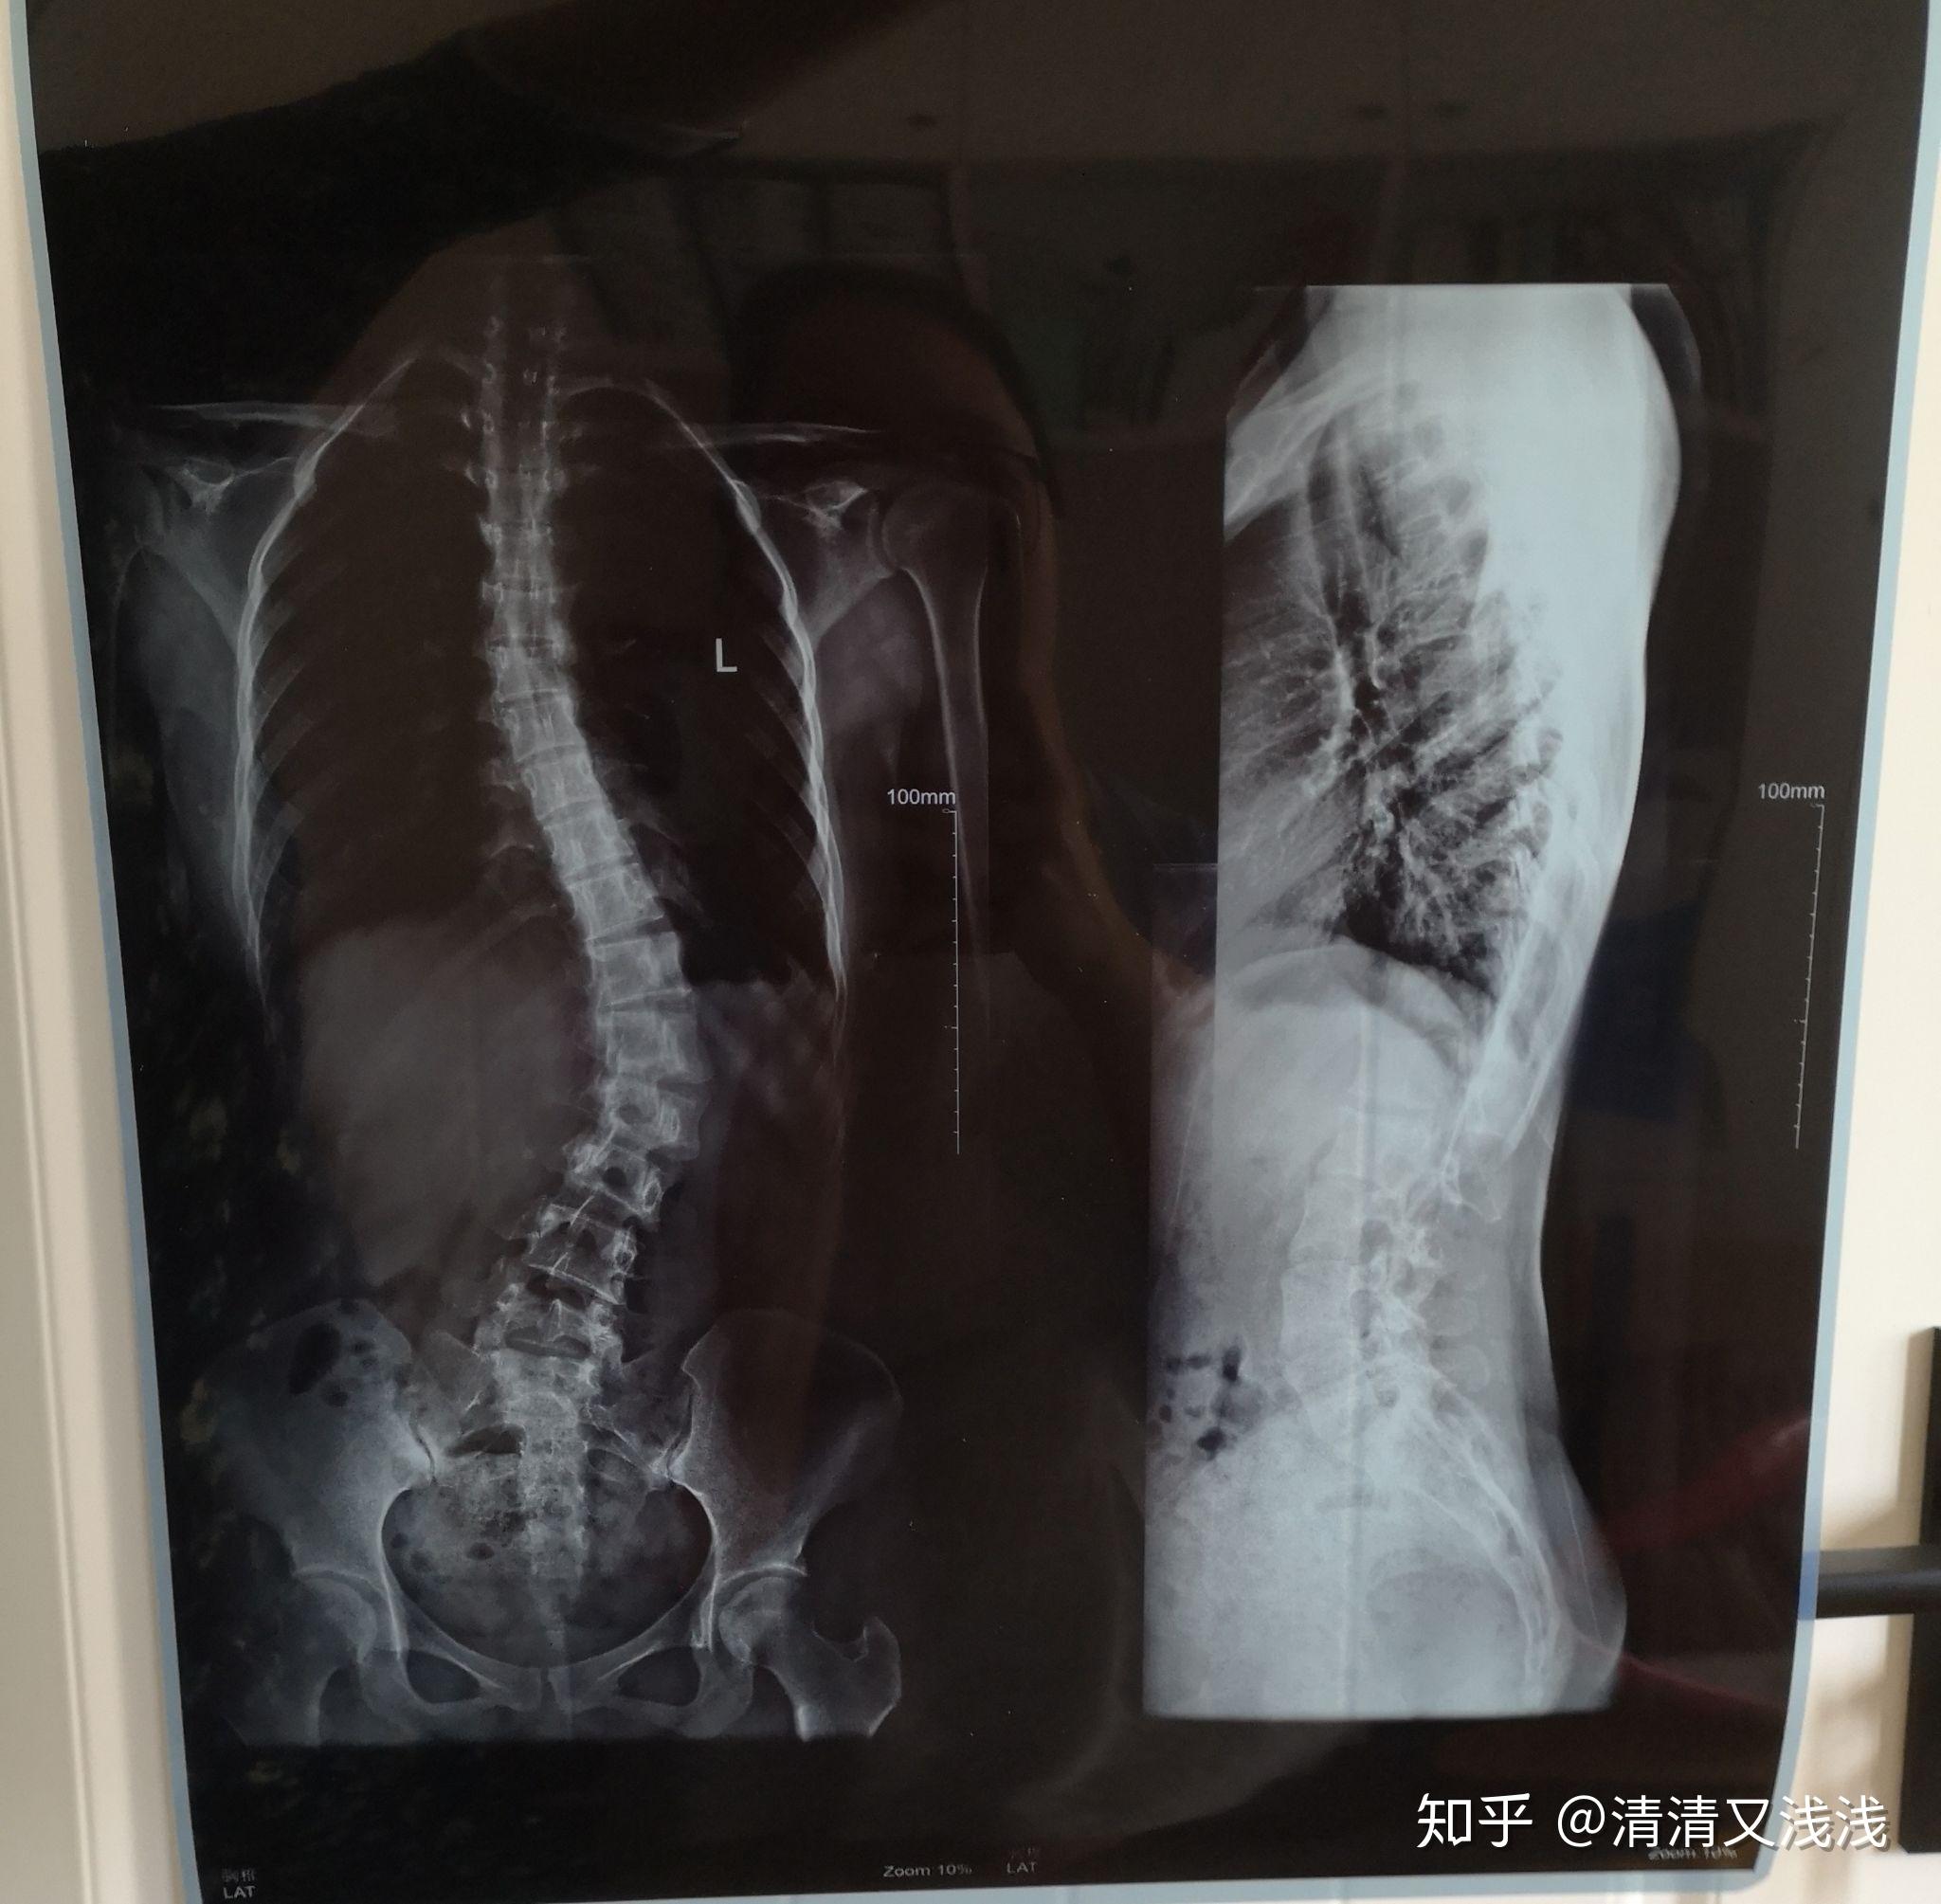

脊柱侧弯矫正3个月剃刀背14度减至0度73

图片尺寸1080x1208